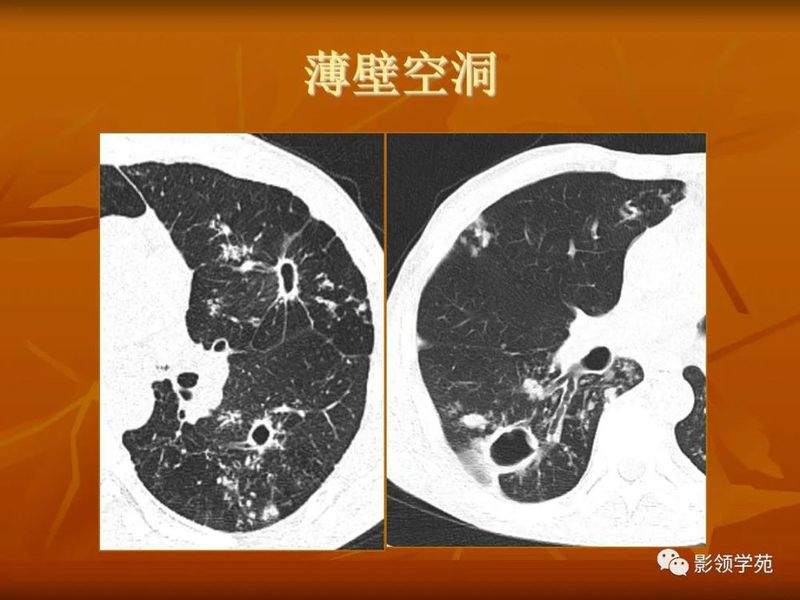

(1)较大含空洞性肿块,洞壁较厚,大于15mm,空洞外壁有分叶、毛刺,洞壁凹凸不平有壁结节,增强可见不规则强化,周围未见明显卫星病灶时,首先考虑周围型肺癌;癌性空洞洞壁一般肺门侧较厚,空洞多偏于外侧,伴有同侧淋巴结肿大更支持肺癌诊断。

(2)空洞病变发生于双肺上叶尖后段、下叶背段,病变周围可见点状、结节状及片状卫星病灶,洞壁组织无明显强化或有包膜线样强化时,考虑结核;结核球的空洞多位于病变的肺门侧,与引流支气管相同,洞内壁一般较光滑。